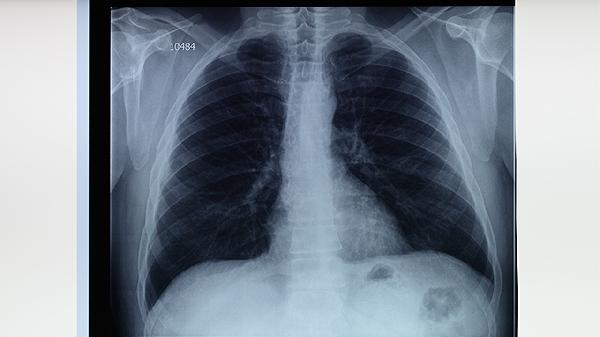

人體免疫系統(tǒng)功能減弱時易發(fā)生肺結核。艾滋病患者、長期使用免疫抑制劑者、糖尿病患者等群體因免疫功能受損,難以有效清除結核分枝桿菌。營養(yǎng)不良、過度勞累等因素也會降低免疫力。這類人群感染后易發(fā)展為活動性肺結核,表現(xiàn)為持續(xù)咳嗽、咯血、胸痛等,需進行胸部X線或CT檢查明確病情。

肺結核典型病理改變?yōu)榻Y核結節(jié)形成和干酪樣壞死。早期表現(xiàn)為滲出性炎癥,隨后形成上皮樣細胞和多核巨細胞構成的肉芽腫,中心發(fā)生干酪樣壞死。病變可鈣化愈合,也可液化破潰形成空洞。這些變化導致患者出現(xiàn)咳嗽、咯血等癥狀,嚴重者可發(fā)生肺組織廣泛破壞。